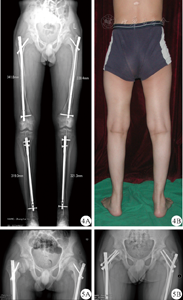

本组17例共接受55例次手术,其中包括16例截骨股骨顺行髓内钉固定术,6例截骨股骨逆行髓内针固定术,17例胫骨带锁髓内针内固定术,有4例在行髓内针截骨手术时应用了附加单皮质钢板增加稳定性;7例胫骨截骨锁定钢板内固定术,6例应用"8"字钢板行胫骨近端骺阻滞术,股骨远端截骨克氏针固定1例,髓内针取锁钉1例,空心钉固定1例(表1)。共39例截骨髓内针固定手术中,有8例股骨仅行单处截骨,有1例胫骨行单处截骨,其余均为多段截骨。因经济及家庭原因,有6例患儿仅接受对畸形最严重的一侧肢体行手术治疗,最终接受带锁髓内针固定治疗的肢体共26侧,其他方法固定的肢体2侧。接受髓内针治疗的肢体中有5侧为膝外翻组,21侧为膝内翻组。所有17例患儿均得到随访,随访时间14~96个月,平均40.5个月;患儿截骨端在4~9个月达到临床愈合(平均6.3个月),恢复正常负重行走。未出现感染、血管神经并发症及不愈合。典型病例可见图3。

对于总计22例股骨髓内针固定手术,有1例术后5个月时因担心骺阻滞效应,行锁定螺钉取出手术,术后1年复查时见截骨愈合良好,但股骨远端截骨端矫正有部分丢失,术后6年随访时畸形无进展。另一例患儿双侧行股骨截骨、顺行带锁髓内针内固定术,术后一年遭遇轻微外伤后出现右侧股骨头骺滑脱,左侧股骨近端髋内翻畸形加重,按照Li等[6]报道的方式行近端锁钉更换、空心钉内固定术(图4、图5)。术后恢复良好,随访4年股骨近端畸形未再加重。

低磷酸血症佝偻病的股骨近端畸形大多为轻度髋内翻,本组均未对髋内翻畸形行粗隆下外翻截骨,故行带锁髓内针近端锁定时,大多数术者采用自大粗隆向小粗隆方向的常规锁定,术后随访也未见股骨近端畸形加重。有3例患儿采用沿股骨颈方向的重建锁定,其中1例于术后一年时因轻微外伤即出现右侧股骨头骺滑脱,左侧髋内翻也有加重。有报道类似的情况在儿童股骨颈骨折内固定术后也曾出现,Li等[6]认为,发生股骨头骺滑脱的原因与骨折复位不良导致的髋内翻、金属内固定位置及过早负重有关。对于此例患儿主要考虑其本身就存在髋内翻畸形,而重建方向的锁定螺钉前端恰位于干骺端(图4),导致此处应力集中;佝偻病使得本身就薄弱的干骺端松质骨区域更加脆弱,因而在负重内翻的剪式应力作用下发生骨骺滑脱。对于此种情况,我们不推荐常规采用重建方向进行近端锁定,若是由于截骨部位偏近端而必须采用重建锁定的方式,则应选择合适长度,使锁定螺钉通过骺板,进入二次骨化中心内完成锁定。